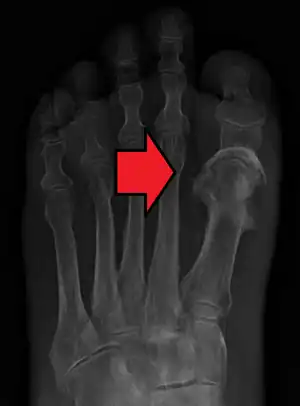

Osteomielite é uma infeção do osso.[1] Os sintomas mais comuns são dor num osso específico, vermelhidão na área sobre o osso, febre e fraqueza.[1] Em crianças, os ossos mais afetados são os ossos longos dos braços e das pernas, enquanto em adultos os ossos mais afetados são os ossos dos pés, coluna vertebral e ancas.[2] A doença pode ser de início súbito ou gradual.[1]

A doença é geralmente causada por uma infecção bacteriana, embora em casos raros possa também ser causada por uma infeção fúngica.[1][2] A infeção pode ter origem nos tecidos envolventes ou ter sido espalhada pela corrente sanguínea.[4] Entre os fatores de risco para o desenvolvimento de osteomielite estão a diabetes, consumo de drogas injetáveis, antecedentes de remoção do baço e trauma na região afetada.[1] Geralmente suspeita-se do diagnóstico com base nos sintomas, podendo ser confirmado por análises ao sangue, exames imagiológicos ou biópsia ao osso.[2]

Os resultados do exame físico e os sintomas podem sugerir osteomielite. A leucocitose sugere infecção. A zona infectada aparece quase sempre anormal numa cintilografia óssea (com isótopos radioativos como o tecnécio), exceto nas crianças; em contrapartida, pode não se manifestar numa radiografia até 3 semanas depois do aparecimento dos primeiros sintomas. A tomografia axial computadorizada (TAC) e a ressonância magnética (RM) também identificam a zona infectada. Contudo, nem sempre distinguem as infecções de outras perturbações do osso. Para diagnosticar uma infecção óssea e identificar a bactéria que a causa, devem colher-se amostras de sangue, de pus, de líquido articular ou do próprio osso. Em geral, numa infecção das vértebras analisam-se amostras do tecido ósseo que são extraídas com uma agulha ou durante uma intervenção cirúrgica.[10]